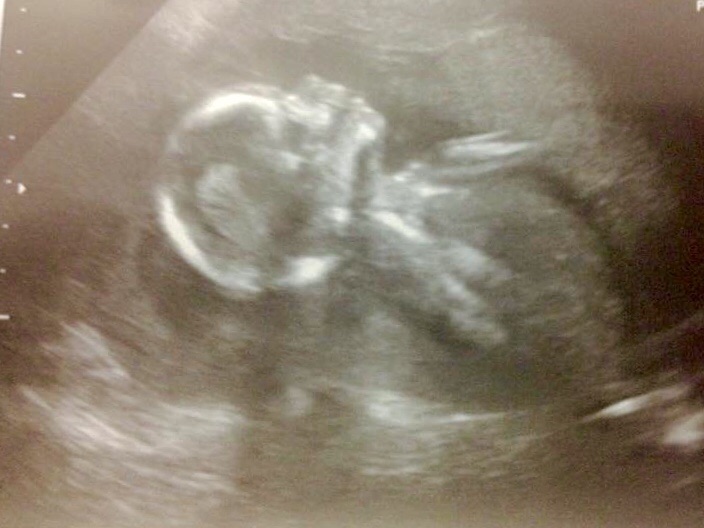

girly guess

Awww!! Beautiful baby profile!!!

Going girl

leaning girl

I feel better using skull closer to 12 but that chin (God knows why) always reminds me of girls so I away girl, skull theory however is not reliable so take my guess as a pinch of salt. Hope you get the gender you wish x

Looks girly

Looks girly, but I honestly don't trust skull theory like I would trust a nub shot.

I don't guess skulls it's too unreliable but just wanted to say this is the sweetest little profile!